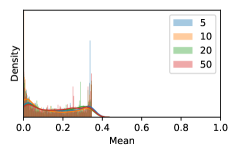

To model how different classifiers will respond to a given input , we assume that the prediction from classifier is sampled from a beta distribution that is characterized by two parameters by and . We further assume that is fixed to the same constant value for all ’s. Under this assumption, each input can be described by ( can be calculated since is fixed), easing further analysis. The Severity Level (SL) of the case represented by image can be characterized by the parameter . The larger the value of , the more severe the case of is. When and are close, the case is ambiguous as the distribution shifts towards being symmetric (i.e. signifying much disagreement among classifiers) rather than being one-sided (i.e. consensus among classifiers that is negative or positive). We provide a set of examples in Figure 2 and also Figure S.8 in the supplementary materials showing how the beta distribution can be used to capture diverse predictions given by an ensemble learner.

In contrast, the MC-dropout method showed the worst overall performance among the three, as it can be seen from the high ratios of SL0 examples among the uncertain negatives in Figure 4. The histograms in Figure 2 provides another perspective to look into the phenomenon, where a decent proportion of MC-dropout model’s predictions on SL0 inputs entailed low confidence (far from 0 or 1), which from another angle explained why MC-dropout was less specific in terms of lower FNP; many no-DR inputs (i.e. SL0) were erroneously assigned high uncertainty by MC-dropout models.

As discussed in Section 5.1 and Section 5.3 in the main paper, the mean metric and the stacking ensemble will have better performance in the precision (specificity) on the ambiguous data. Here, more detailed results are shown in Figures S.3 & S.6 and Table S.1. Figures S.3 & S.4 show the histograms of the uncertainty score for Kaggle-DR and Messidor-2 datasets that are the in-distribution (i.d.) dataset in our experiment and FigureS.5 & S.6 show the histograms for ImageNet and CIFAR-10 datasets, which is the o.o.d. datasets in our experiment. Each group of histograms contains results from the three evaluated ensemble methods (stacking ensemble, MC-dropout and TTA) and the three uncertainty metrics (mean, var and kl). Additional detailed results not displayed in Figure 4 can be found in Table S.1, which shows the proportion of the data of different SLs varies across different . For comparison, we also included in Table S.1 the results from single learners, and the proportions of data of different SLs (before any selection was made).